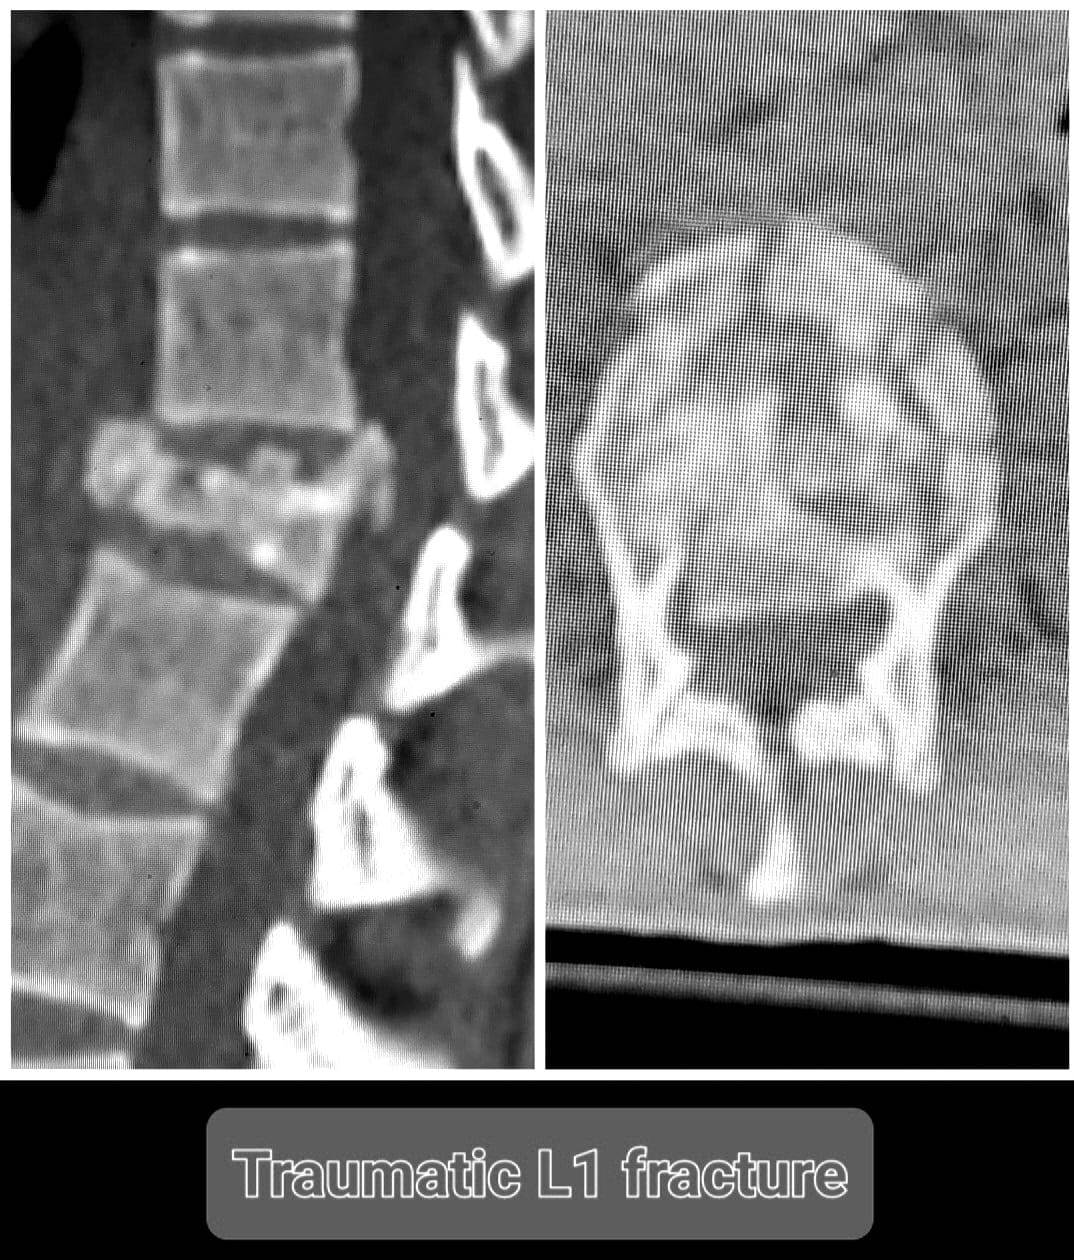

وأعلن الدكتور تامر حمدى أحمد مدير عام المستشفى في بيان ) عن قيام الدكتور صلاح صبرى محمد صلاح مدرس مساعد جراحة المخ والأعصاب بمستشفيات جامعة الزقازيق .. يرافقه الدكتور محمود الوكيل مدرس التخدير بالقصر العينى جامعة القاهرة .. بإجراء جراحة عاجلة لمريضة تعانى من كسر في الفقرة القطنية الأولى ضاغط على الحبل الشوكى .. مما نتج عنه ضعف في حركة الطرفين السفليين ، وأنه على الفور تم عمل الاشعات اللازمة للمريضة ودخولها غرفة العمليات لتثبيت الفقرات الصدرية والقطنية بواسطة شرائح ومسامير وتوسيع القناة العصبية وإزالة الضغط على الحبل الشوكى .. مشيرا الى استمرار الحالة بالمستشفي حتى استقرت وتحسنت حركة الطرفين السفليين لها .